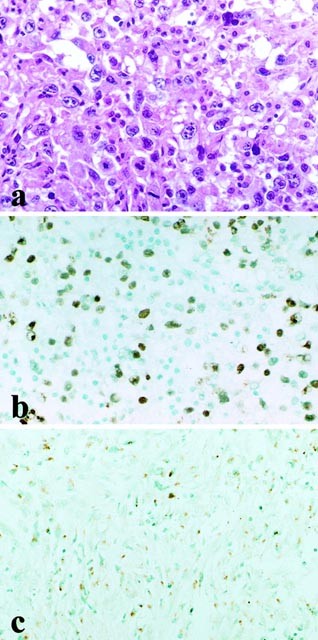

In normal pituitary glands, immunostaining of RCAS1 and MIB-1 was not found. In malignant glioma, a large number of cells were positive for MIB-1 (MIB-1 index: 28%), and RCAS1 was detected both in the cytoplasm and on the membrane of the most of tumor cells (Fig. 1). Expression of RCAS1 was noted in 48% of pituitary adenomas stained by immunohistochemistry (Fig. 2) (60.0% of growth hormone-secreting adenomas, 60.0% of prolactin-secreting adenomas, 42.9% of adrenocorticotrophin-secreting adenomas, 40.0% of thyroid-stimulating hormone-secreting adenomas, 33.3% of nonfunctioning adenomas, and 44.4% of gonadotropin-subunit-positive adenomas). Kruskal-Wallis test proved no statistical correlation between immunohistochemical expression of RCAS1 and types of pituitary adenomas (Table 1). Expression of RCAS1 showed 48.0% of microadenomas and macroadenomas. RCAS1 showed 31.6% of noninvasive adenomas and 58.1% of invasive adenomas. Expressions of RCAS1 were not correlated with tumor size and invasiveness (Tables 2 and 3). Relationship between RCAS1 expression and MIB-1 index was statistically proven in this study (Fig. 3). The mean MIB-1 index values ± SD were found: RCAS1-positive adenomas (n = 24), 1.222 ± 1.067; RCAS1-negative adenomas (n = 26), 0.326 ± 0.311% (P <.001). [Table 4 ]